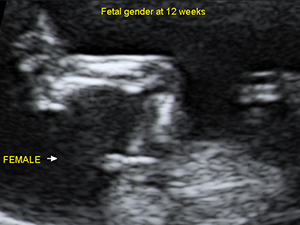

Female genital organ (arrow) at 12 weeks Second Trimester - Head and Face